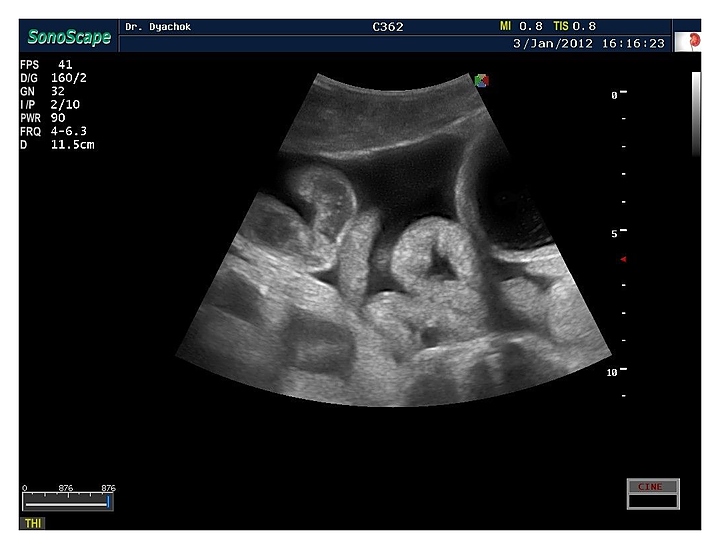

Узи кишок как называется

Узи кишок как называется 119 фото